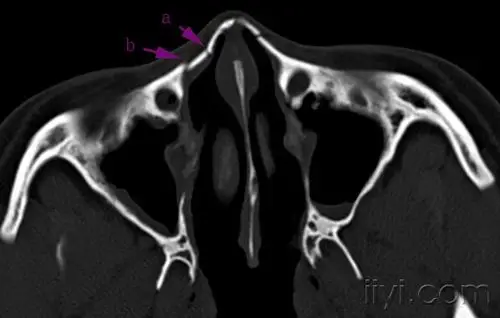

清晰图讲解鼻骨骨折影像学诊断

鼻骨骨折影像学诊断与鉴别

鼻骨骨折影像学诊断

鼻骨骨折ct影像学-医学影像图

鼻骨骨折